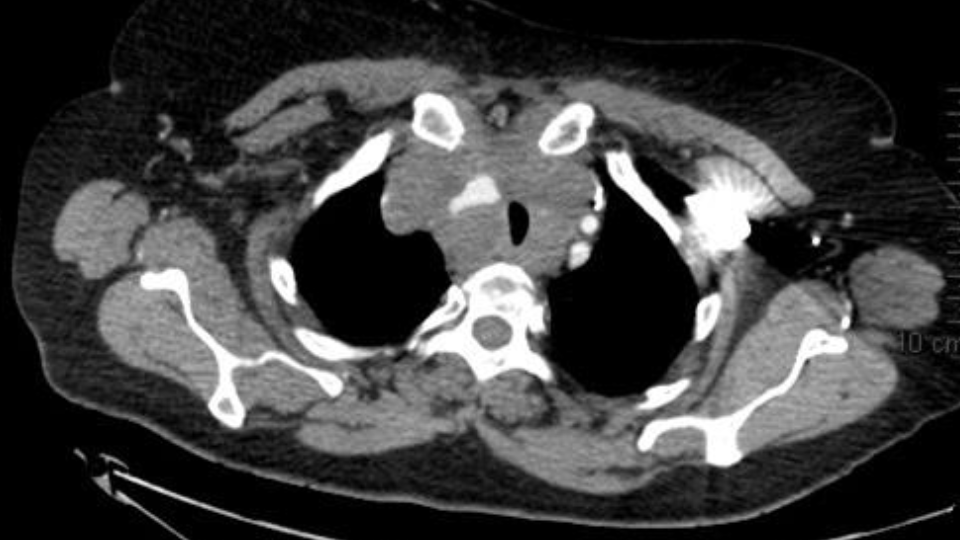

Dans cette revue de la littérature, nous développerons, au niveau diagnostique l’abord médiastinal endoscopique avec l’echoendoscopie bronchique (EBUS) et l’approche des nodules pulmonaires de l’endoscopie simple à l’endoscopie robotique.  Au niveau thérapeutique, nous abordons l’intérêt de la bronchoscopie rigide dans la désobstruction des voies aériennes principales qui pourrait changer le pronostic du patient.